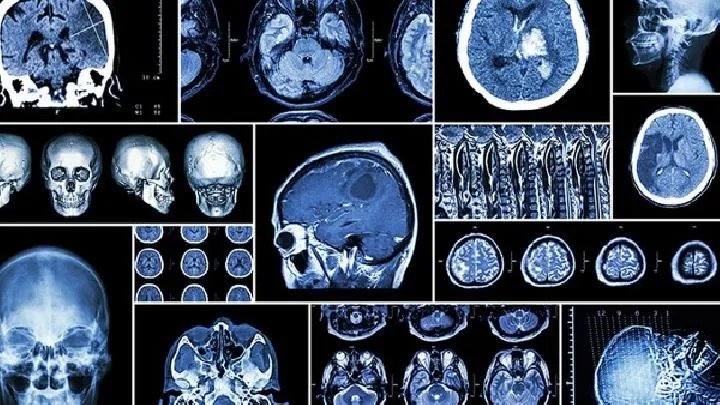

脑水肿应该如何预防

的有关信息介绍如下:脑水肿主要是由颅内疾病或全身疾病引起的。